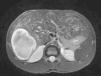

En las pruebas de imagen realizadas, ecografía abdominal y RM abdominal se pone de manifiesto una hepatomegalia a expensas de múltiples lesiones intrahepáticas alguna de ellas con componente hemorrágico y otras claramente quísticas compatible con peliosis hepática (fig. 1).